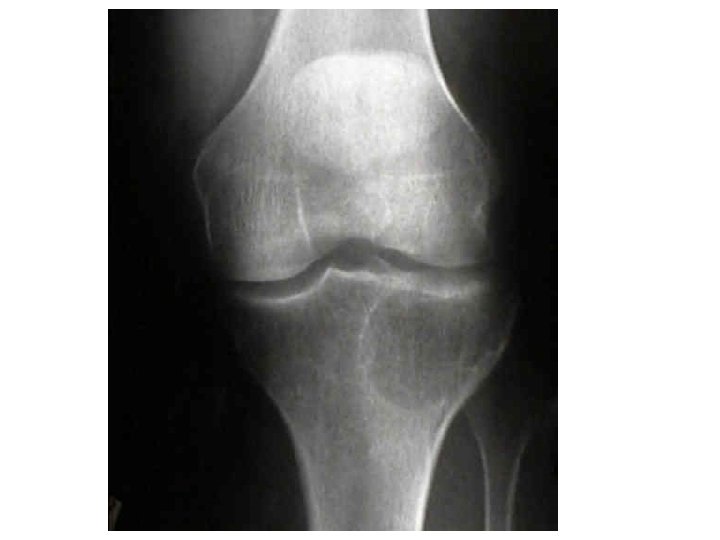

Joints A joint, or articulation, is the place where two bones come together. • Fibrous- Immovable: connect bones, no movement. (skull and pelvis). • Cartilaginous- slightly movable, bones are attached by cartilage, a little movement (spine or ribs). • Synovial- freely movable, much more movement than cartilaginous joints. Cavities between bones are filled with synovial fluid. This fluid helps lubricate and protect the bones.

Types of Joints Hinge- A hinge joint allows extension and retraction of an appendage. (Elbow, Knee)